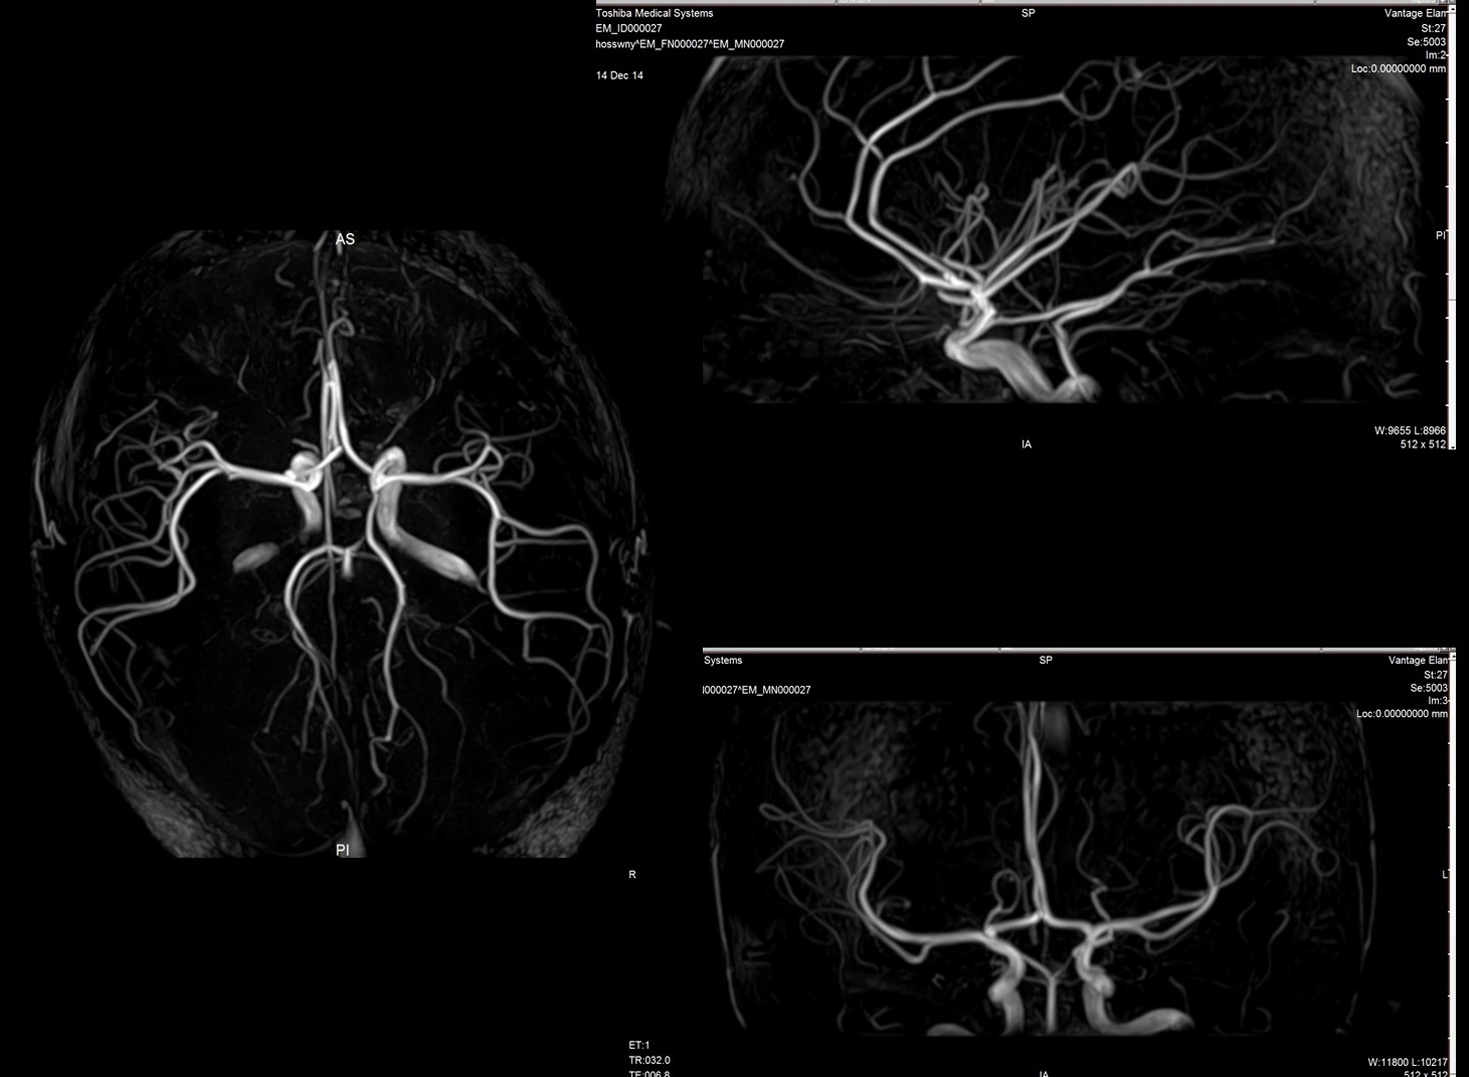

From www.researchgate.net

3D image brain MRA without contrast utilizing timeofflight (TOF How Does Mra Work Without Contrast during magnetic resonance angiography, you lie flat inside the magnetic resonance imaging scanner. This makes it very valuable. In some cases, a special dye, known as contrast, may be added to your bloodstream to make your blood vessels easier to see. in this review article we consider the motivations for using noncontrast mra, potential contrast mechanisms, imaging. . How Does Mra Work Without Contrast.